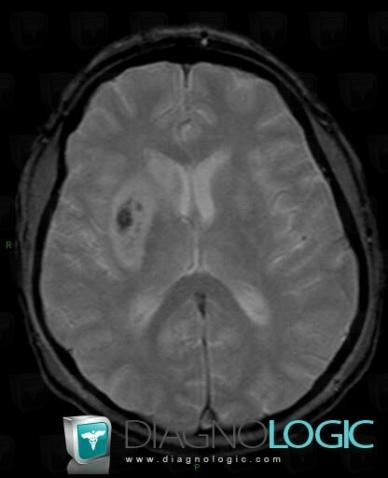

Cerebral infarction, Basal ganglia and capsule, MRI

Here is the specific information in the key image above:

- Diagnosis Cerebral infarction, Location(s) Basal ganglia and capsule, with gamuts Basal ganglia T2W or FLAIR hyperintense lesion